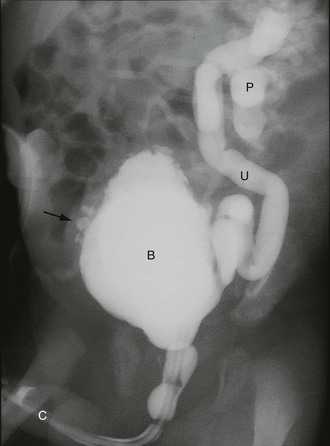

Fig. 51.6 Vesicoureteric reflux

Micturating cysto-urethrogram (MCUG) in a child with recurrent urinary tract infections. The bladder B is trabeculated (diverticula arrowed). On voiding, the left ureter U and pelvicalyceal system P filled with contrast as a result of severe dilating vesicoureteric reflux. This is defined as grade V reflux